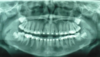

what type of PA is this

maxillary PM PA

want to see the contacts of D of C/PM, PM/PM, and 2ndPM/M